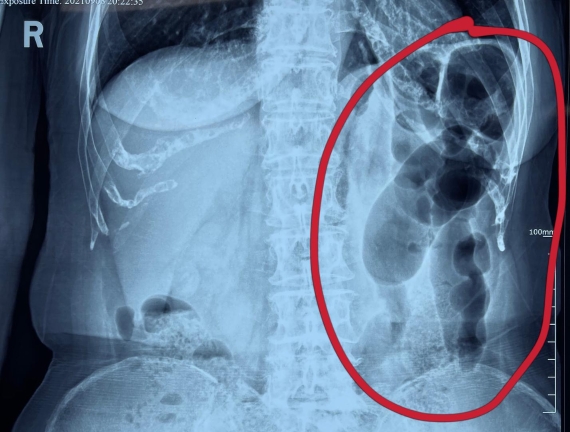

據(jù)省醫(yī)院消化病院消化二科姜子曄醫(yī)生介紹,韓大娘今年已經(jīng)73歲,家住哈爾濱市,一周前開始腹脹腹痛,有較為明顯的左側(cè)腹部疼痛,疼痛劇烈時會出現(xiàn)左側(cè)腹部鼓包情況,排氣排便后有所好轉(zhuǎn)。韓大娘家人見狀將其送到了黑龍江省醫(yī)院,門診檢查腹部平片提示為左側(cè)腹部積氣,口服全消化動力藥及通便治療后腹痛腹脹有所緩解,入院前再次突發(fā)左側(cè)腹痛加重伴有明顯腹脹,急診隨后以“腹痛腹脹原因待查”將韓大娘收入到消化病院消化二科。

姜子曄醫(yī)生熱情接待了韓大娘,為其進行了仔細查體,除了左側(cè)腹部壓痛并未見明顯異常,對癥給予灌腸后,韓大娘的腹脹有所緩解,第二天姜子曄醫(yī)生為韓女士進行了胃腸鏡檢查,也未見明顯異常。但此時韓大娘腹部平片結(jié)腸腸管擴張仍然很嚴(yán)重,腹痛腹痛也沒緩解,到底什么原因呢?消化二科主任陸以霞在查房時建議繼續(xù)給予韓大娘口服全消化動力藥,必要時灌腸治療,同時陸以霞主任在追問病史查體時發(fā)現(xiàn)韓大娘左下腹紅色皮疹和小水泡,反復(fù)抓撓腹部皮膚部分已結(jié)痂,高度懷疑為帶狀皰疹。